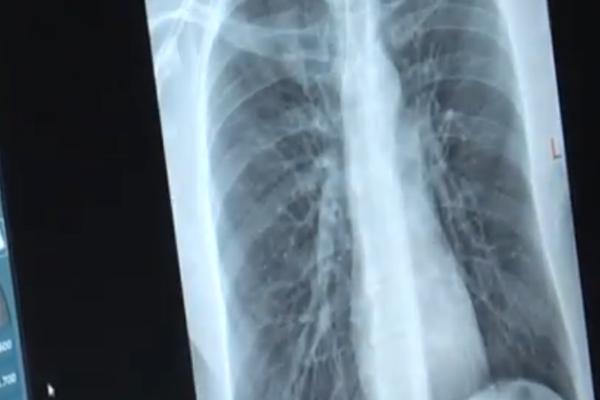

DEČAK JE HITNO PREVEZEN U BOLNICU! KAD SU DOKTORI URADILI RENDGEN, umalo se nisu ONESVESTILI!

DEČAKA (7) HITNO PREVEZLI U BOLNICU: Doktori su odmah uradili rendgenski snimak, u njegovom želucu su pronašli OVO!